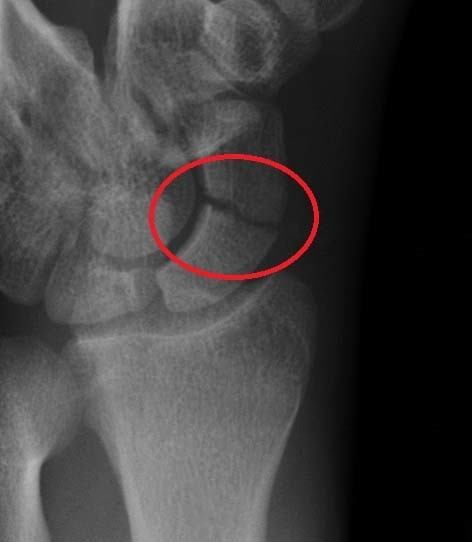

Clinical relevance - scaphoid fracture?

THe scaphoid bone of the hand is the most commonly fractured carpal bone - typically by falling on an outstretch hand.

In a fracture of the scaphoid, the characteristic clinical feature is pain and tenderness in the anatomical snuffbox.

The scaphoid is at particular risk of avascular necrosis after fracrure because of it so-called ‘retrograde blood supply’ which enters at its distal end. This means that a fracture to the middle (or ‘waist’) of the scaphoid may interrupt the blood supply to the proximal part of the scaphoid bone rendering it avascular.

Patients with a missed scaphoid fracture are likely to develop osteoarthritis of the wrist in later life.